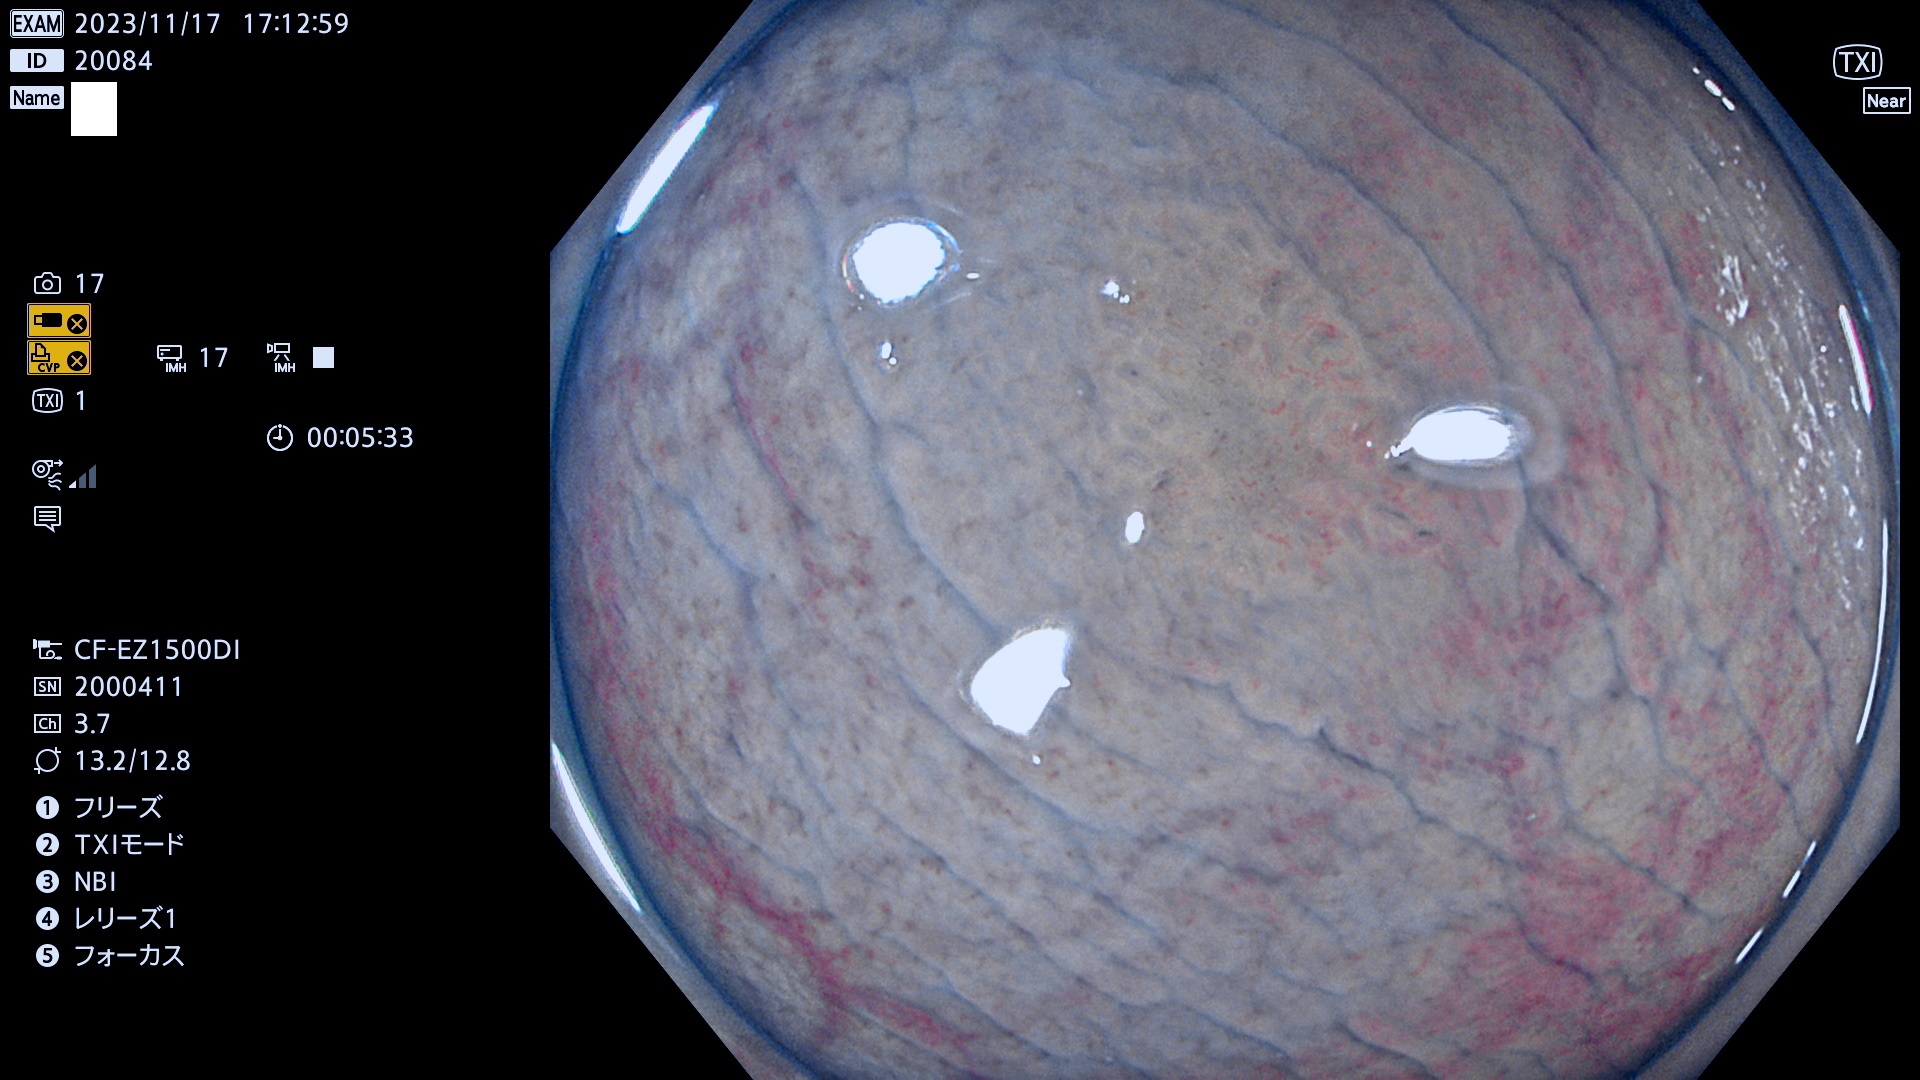

表面型腺腫(Flat Adenoma)の中で、完全に平坦な物をUb、陥凹している物をUcと呼びます。平坦隆起型(Ua)よりも、発見が難しく危険な病変です。このタイプは「内視鏡後・大腸癌の重要犯人」であり、この発見率は「腺腫発見率」よりも、重要な意味があります。

毎週の検査(木・金・土・日)に発見されたUb、Uc型・腺腫を、その週の日曜の夜にUPし1週間、提示します。

抽出の対象期間 2023年11月16日(木)〜11月20(日)の5日間(60件の検査)11件